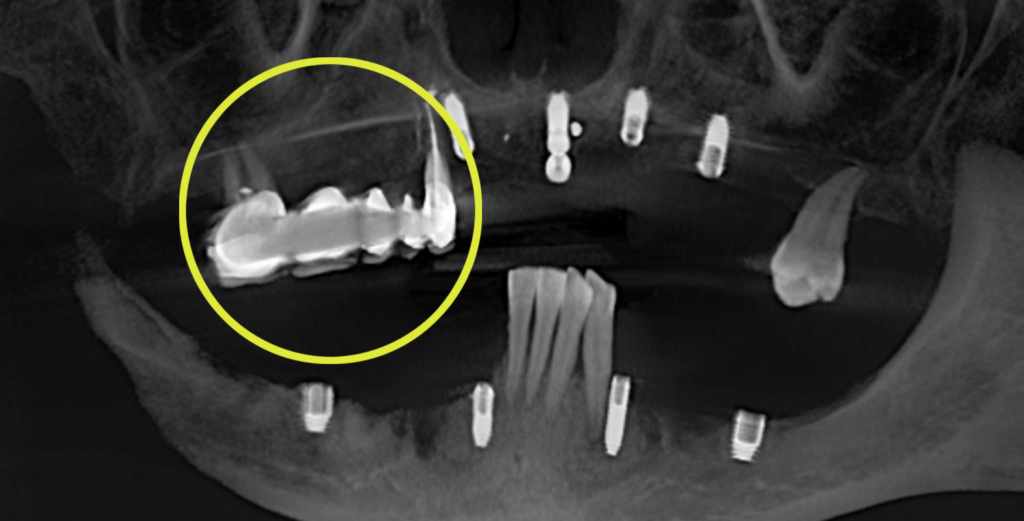

Согласно данным на снимке импланты были расположены не в одной плоскости (нарушена параллельность) и это могло вызвать сложность при протезировании цельнолитой конструкцией, однако при слаженной работе врача и зубного техника был шанс получить положительный результат.